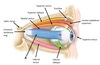

Name muscles A and B

A - Superior oblique

B - Inferior oblique

Name muscle A

A - Superior rectus

Name muscle A

A - Inferior rectus

Name muscle A

A - Medial rectus